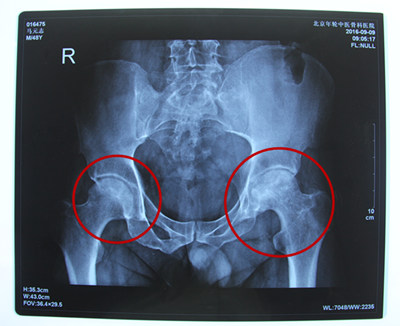

诊断结果:双侧股骨头缺血性坏死

病情描述:患者于2年前因劳累后自觉双髋关节疼痛,以左侧较重,2014年因疼痛加重,就诊于当地医院,经影像检查后确认为双侧股骨头缺血性坏死,经当地医院行左侧股骨头减压手术后疼痛未见好转。2016站立计划走进青海省,通过当地的残联了解到患者的身体及家庭情况。

经特殊批准让他得到了站立计划的全额救助,来到北京年轮中医骨科医院接受治疗。经年轮股骨头医师会诊后决定对股骨头坏死病变区进行左髋关节滑膜切除、清理并修正松解;同时取髂骨进行骨移植微创治疗,并辅以特制中医中药调理病况,由康复医师指导日常髋关节功能的恢复。